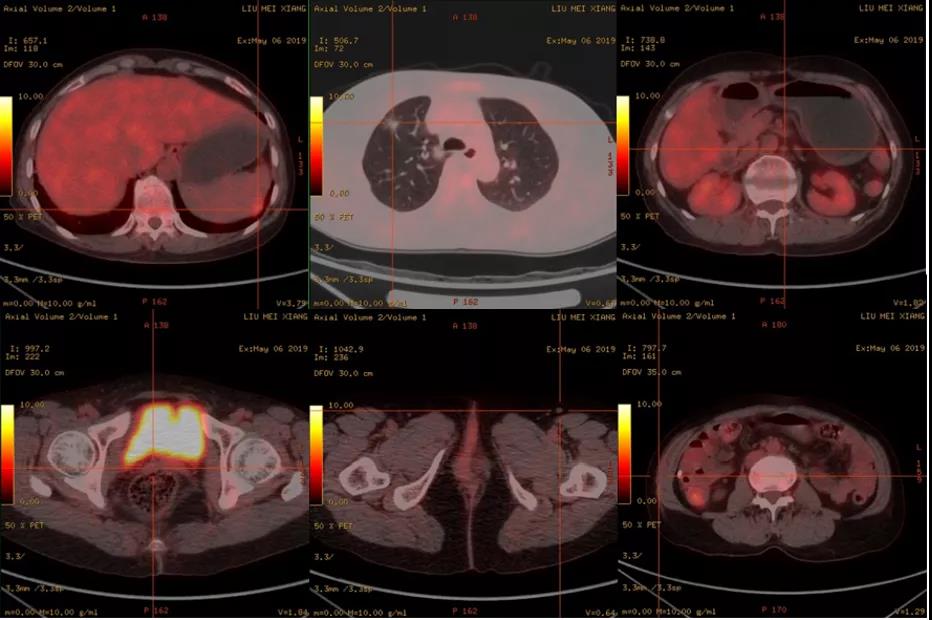

患者服用替吉奥期间,CA-125一度下降至正常范围,但第三个月复查CA-125 200.9 U/ml(图6)。再次行PET-CT显示:1.脾脏包膜下局部片状稍低密度影,代谢增高,结合病史考虑为肿瘤转移性病变可能。2.右肺上叶、左肺下叶磨玻璃影,部分代谢增高,不排外为肿瘤性病变可能。3.右肺中叶、右肺下叶、左肺多发微小结节或结片、半片状影,部分代谢增高;纵隔小淋巴结增大,代谢无增高,上述部分较前相仿。4.右侧腰腹壁皮下片絮状影,代谢轻度升高、考虑炎性改变可能;阴道残端代谢无增高(图7)。此时该患者确诊为第二次临床复发。

图7 2019年5月患者PET-CT结果